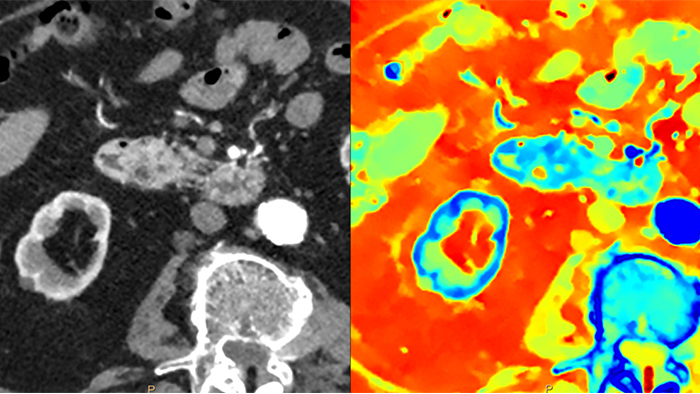

A diferencia de la imagen tomográfica convencional, las imágenes del TAC espectral basado en detección capturan información espectral el 100% de las veces, sin planificación ni configuración especiales. De este modo, puede analizar los datos espectrales de cualquier imagen de forma retrospectiva con diversas herramientas de visualización espectral. Por ejemplo, puede ajustar el nivel monoenergético u obtener mapas Zeffective.

El detector espectral absorbe y diferencia simultáneamente la energía alta y baja de un único haz de rayos X polienergético. Los resultados espectrales se adquieren en una sola exploración sin necesidad de modos especiales.

El TAC espectral basado en detección absorbe y diferencia simultáneamente la energía alta y baja de un único haz de rayos X polienergético a nivel de detector.